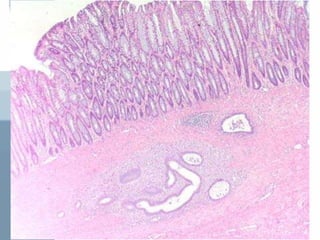

• Microscopically: 2 out of 4 must be

present in the biopsied specimen to

confirm Dx

1- endometrial epithelium

2- endometrial glands

3- endometrial stroma

4- hemosiderin laden macrophages